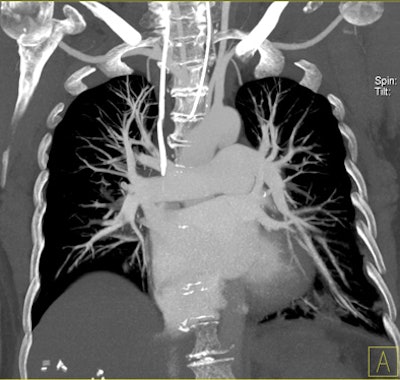

| Patient with bilateral segmental and subsegmental PE and large perfusion defects on dual-energy iodine distribution maps. All images courtesy of Dr. Ralf Bauer. |